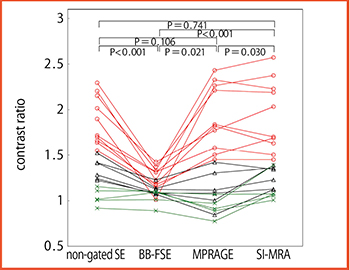

そこで,CEA術前患者を対象に,4種類の撮像法によるT1WIと手術標本を比較し,各撮像法のプラーク描出能を検討した1),2)(図1)。その結果,black-blood FSE法は,心電図同期や複数IRパルスによりTRが延長・変動するため,コントラストが低下して性状判定が困難だった。また, MP-RAGEは,血液信号抑制のためのIRパルスによりT1が血液に近い脂質・壊死成分の信号も抑制してしまうという問題があった。

図1 撮像法(T1WI)の直接比較

文献1)より引用転載

一方でSE法は,プラーク性状ごとにコントラストの差が明瞭であり,病理ともよく一致することから3),プラークイメージングには,通常のSE(FSE)法T1WIが適していると考えられた。ROC解析でも,SE法T1WIは線維・脂質・出血主体プラークを高い感度・特異度で識別可能であった3)。また,T2強調画像(T2WI)は脂質が高信号に描出されるため,線維との識別の参考になった。